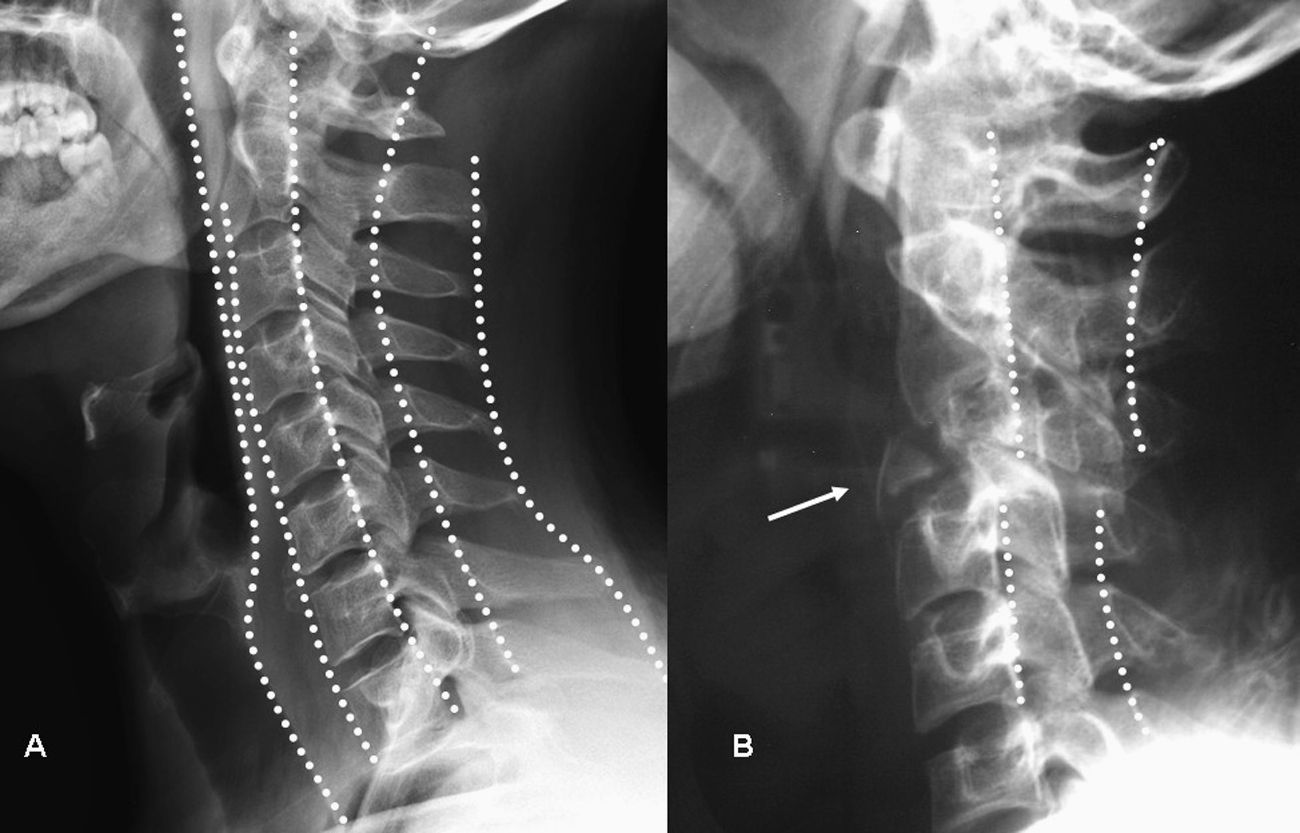

El objetivo de este trabajo es realizar una revisión general de las manifestaciones en la radiografía simple del amplio espectro de patologías que pueden ser responsables del dolor generado en la columna vertebral. Este espectro abarca la patología congénita, traumática, degenerativa, tumoral, inflamatoria e infecciosa.

The aim of this article is to review the manifestations on plain-film radiography of a wide variety of diseases that can cause back pain, including congenital, traumatic, degenerative, tumor-related, inflammatory, and infectious diseases and processes.